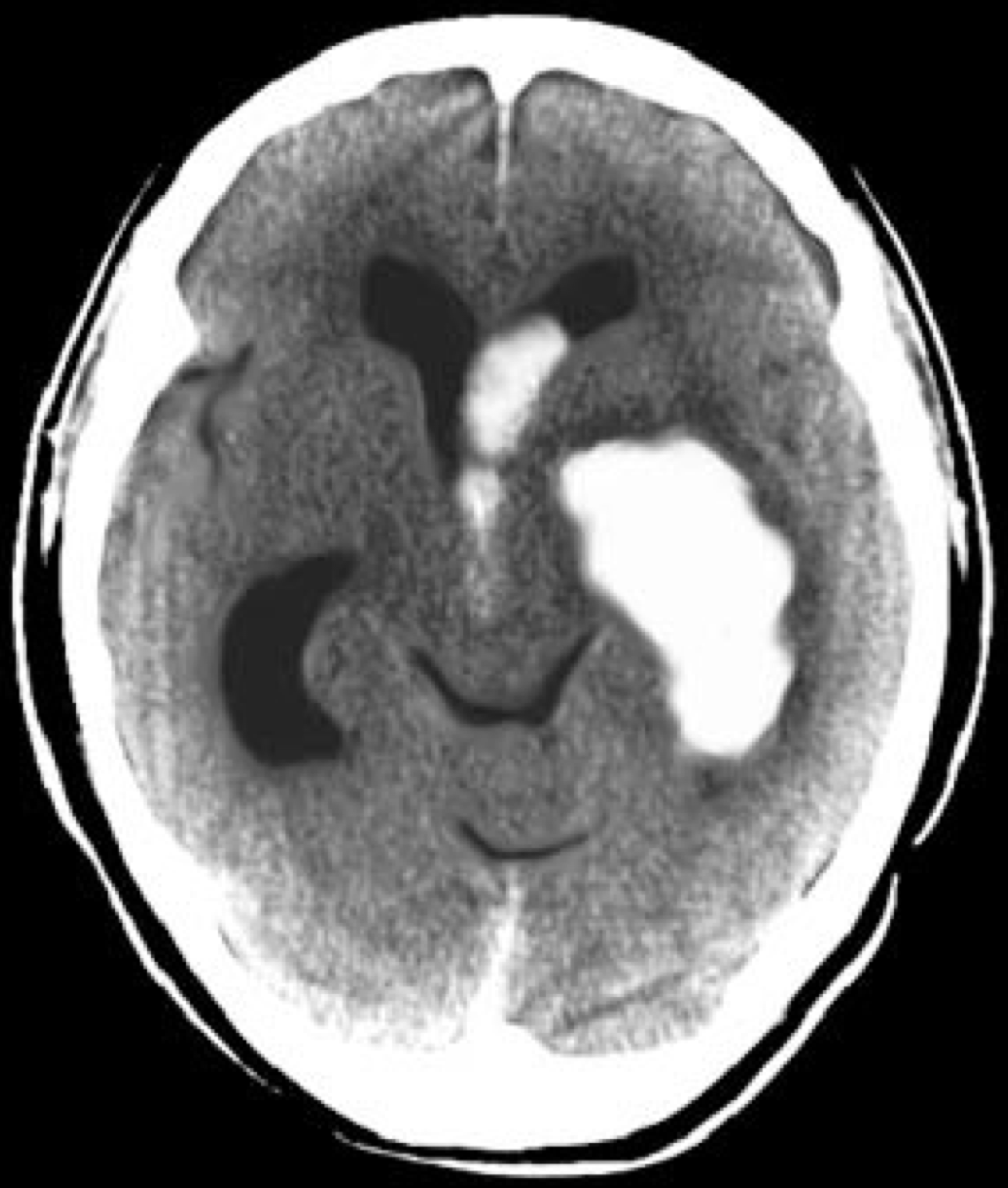

脳出血の頭部CT

生活習慣病の健診は将来の脳血管疾患(脳梗塞・脳出血・くも膜下出血)や虚血性心疾患(心筋梗塞・狭心症)だけでなく、認知症の発症にも大きく関与していると言われており、重要な健診です。